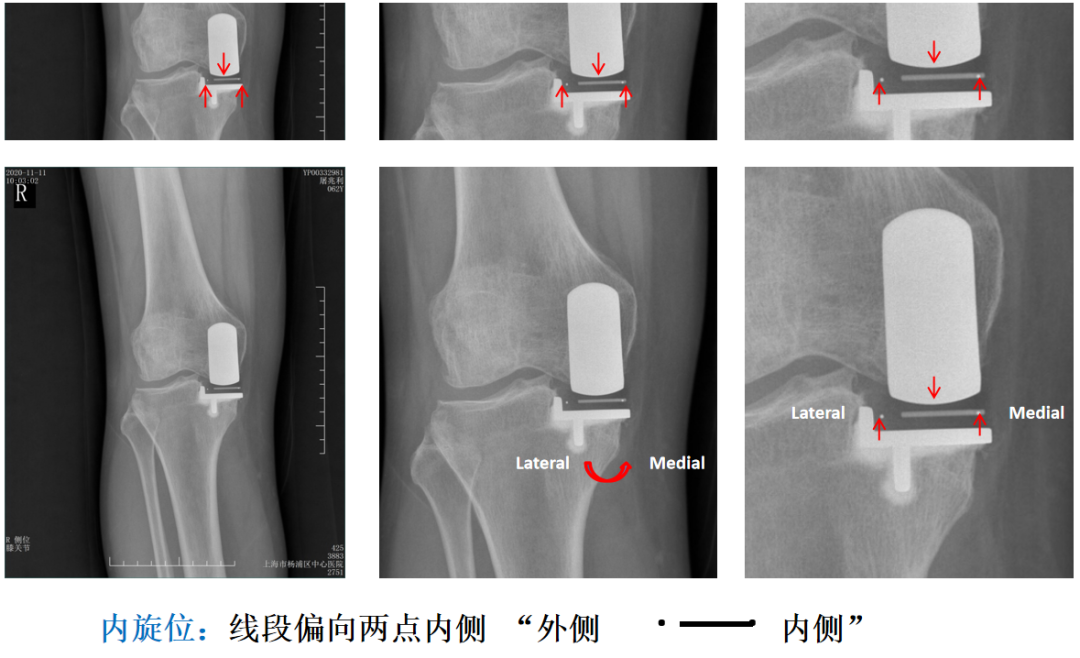

Bearing 内旋( X-ray正位)

Bearing 外旋( X-ray正位)